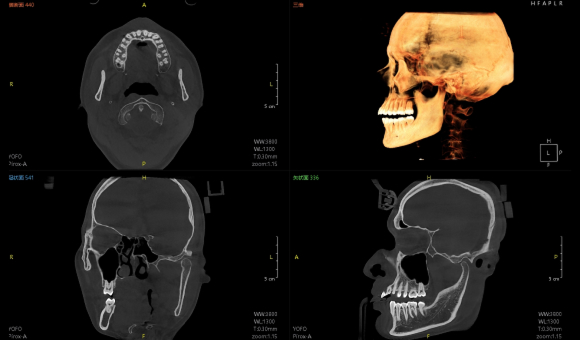

实现非拼接大视野成像

Pirox-A采用多射源并行扫描技术,360°扫描一圈,即可实现非拼接超大视野成像。

实现3D“一成三”成像

单圈扫描可同时获得CT、3D全景及3D正侧位影像,患者无需多次摆位。

视野最大可至24×21cm

视野最大可至24×21cm,即使对于体型偏胖、脸型较大的患者,也都游刃有余。多种视野范围可供临床选择:24×21cm、16×13cm、5×5cm。

24×21的视野,可以完全覆盖患者上至额顶、下至颈角部位,前至鼻尖的范围